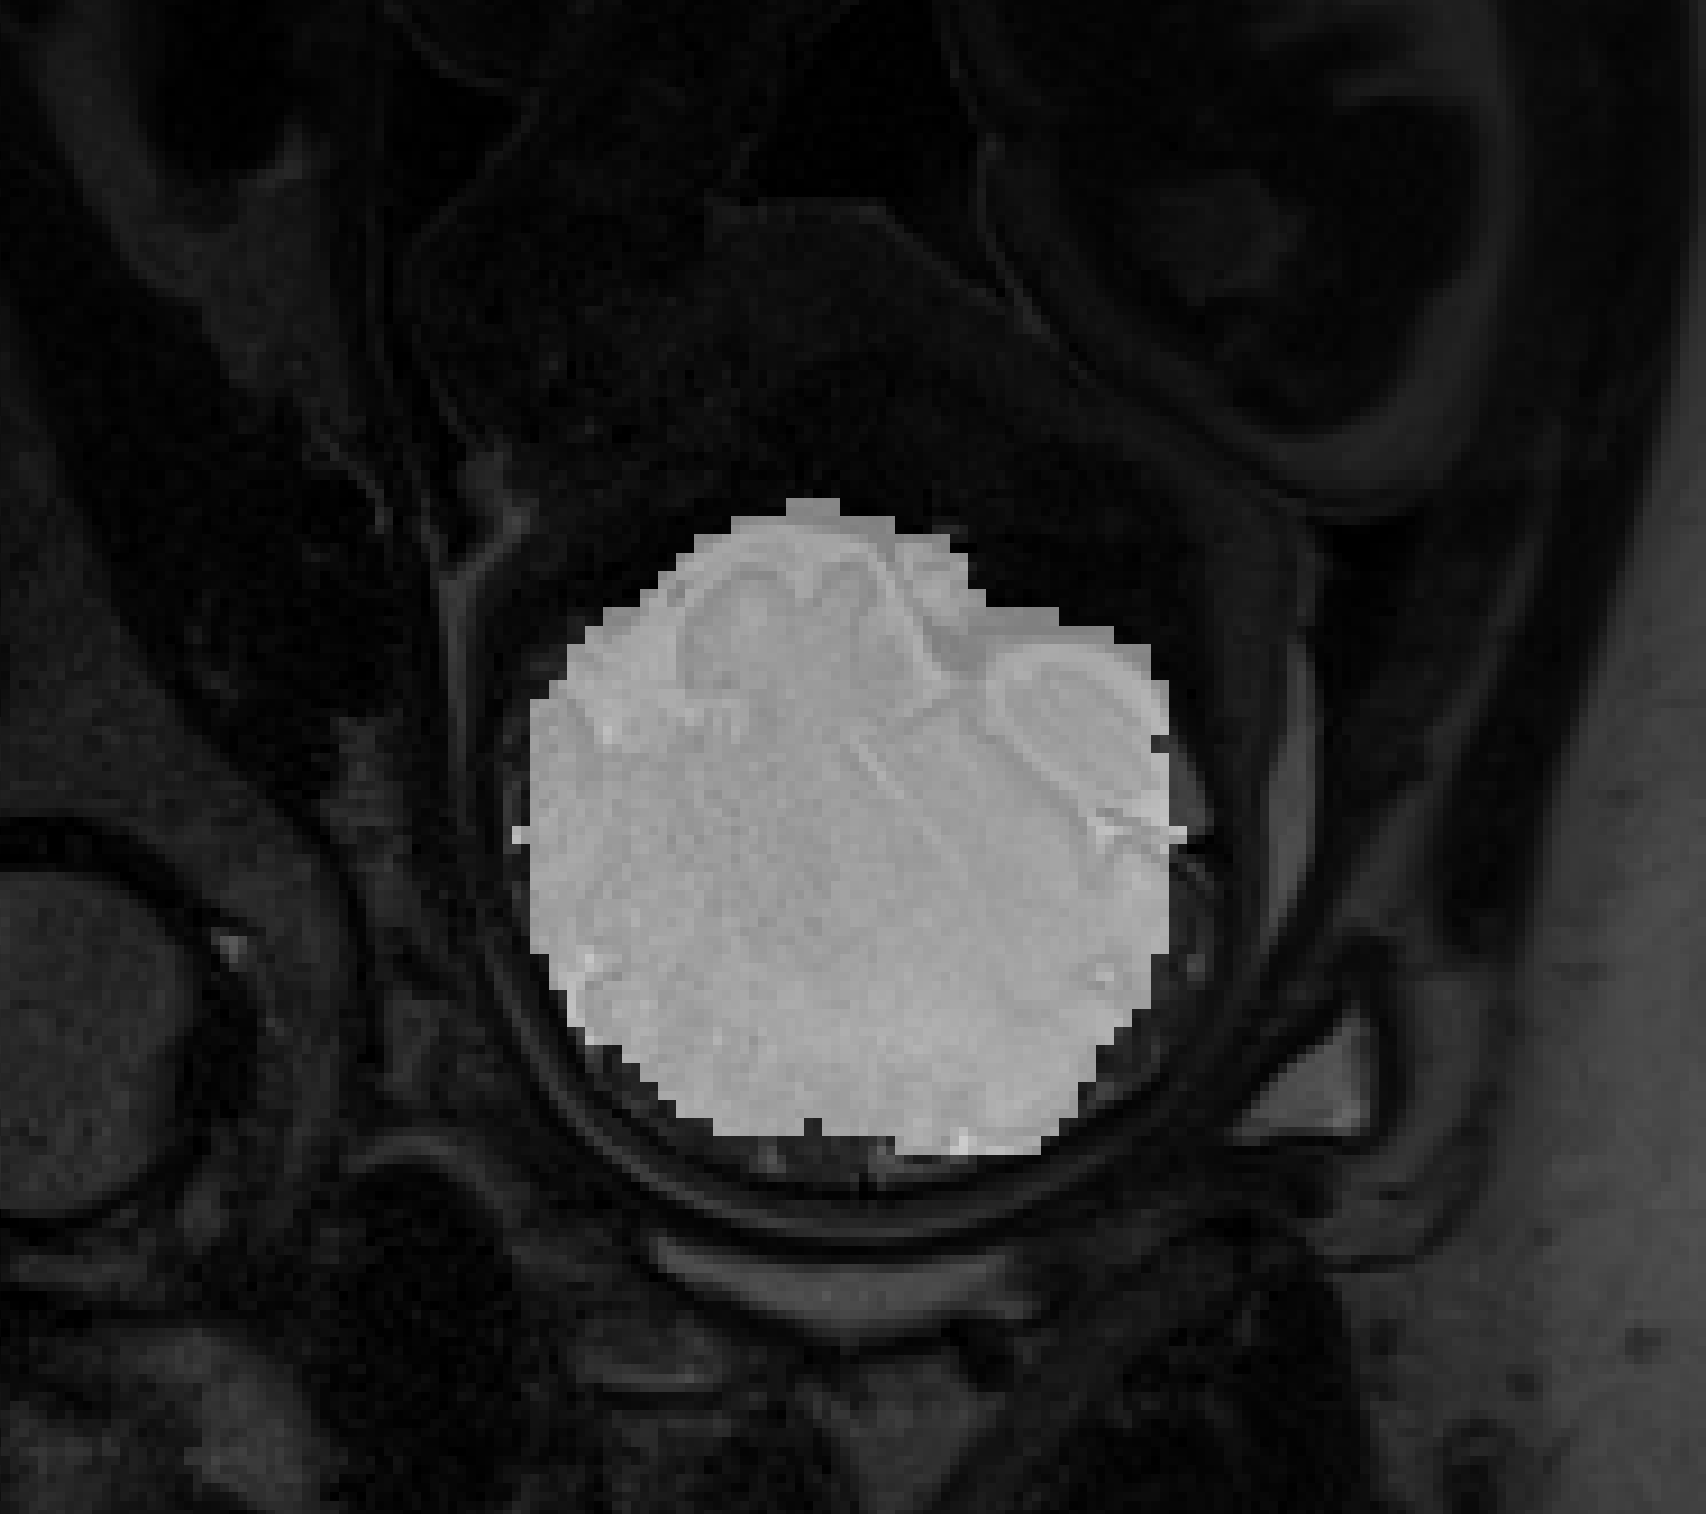

As the pipeline and methods used were configured, we evaluated all the models listed. On the basis of these findings, we chose Attention-Squeeze-Unet as the final. The model has reached a high Dice score on the test data set relative to the baseline Unet. It has also shown the best energy per epoch ratio. To justify our choice, we present graphs of the performance of the model relative to energy consumption in Figures 2 to 4. We also report the segmentation to highlight qualitatively how noisy were the data, as depicted in Figure 1, where the overlay between an original MRI slice and a segmented results are showing, pointing out how cumbersome the data were and how challenging would be to obtain higher Dice score.